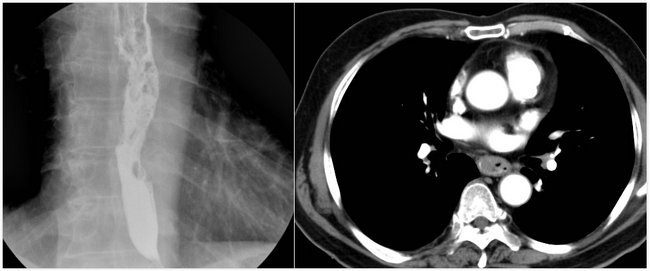

为了进一步明确诊断,评估病情,入院后邢志嵩副主任医师治疗组为患者安排了上消化道造影(图一)、增强CT(图二)等检查,明确为食管中段占位,病变较长,切片经病理科会诊提示:中分化鳞癌(图三)。

▲图一 ▲图二